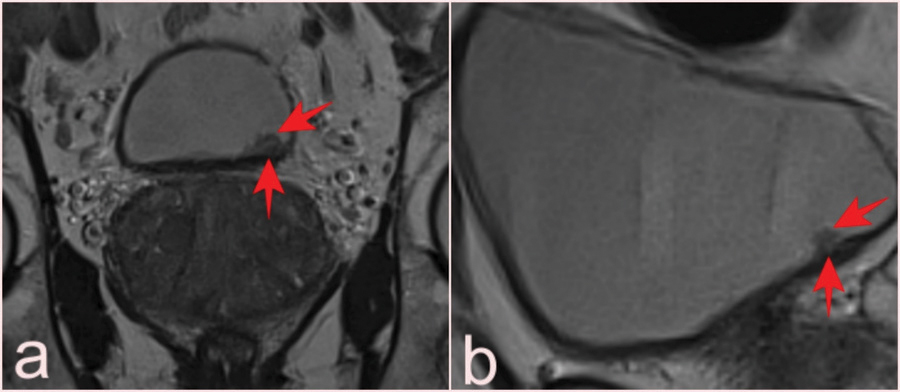

Figure 4

(a, b) Two slices from T2-WI of a 69-year-old patient who presented with elevated PSA and had a total of 10 lesions with pTa pathology, four of which were reported as VI-RADS 1 and six as VIRADS 2 (arrows). Fat-suppressed T2-WI (c) and (d) DCE images of a 75-year-old man with a serum PSA value of 8.9 ng/mL and Gleason score of 3 + 3 prostate cancer, with a lesion reported as VI-RADS 5 but pathologically as a high-grade pT2 tumor (arrows).